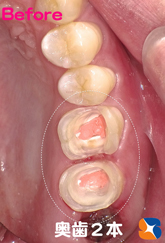

早速、治療開始。親知らずは抜歯。残りの奥歯2本は、神経を抜く治療を行いました。左の写真は、出発3日前(治療回数4回目)の状態です。この状態ではまだ噛めません。

〈写真左〉出発3日前